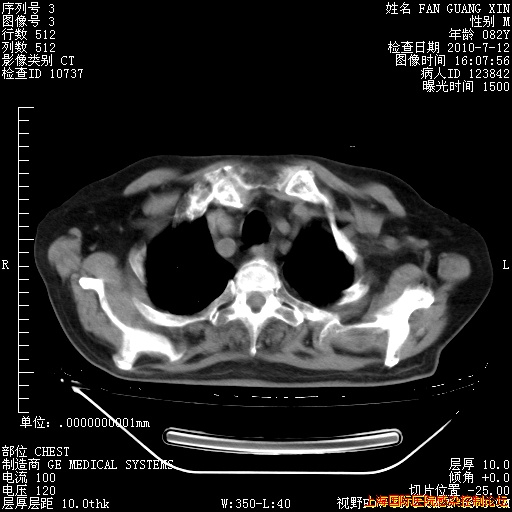

补发6月12日肺部CT肺窗

回复